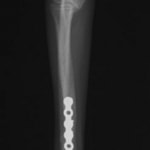

症例3:キルシュナーワイヤーのピンニングによる整復

ペルシャ猫 11ヶ月齢 雄

他院にて左大腿骨遠位の成長板骨折(salter-harrisⅠ型)が認められており、治療相談を目的として来院。当院にて、キルシュナーワイヤーを用いたピンニングにより骨折部位の整復を行いました。術後の経過は良好で、現在も経過観察中です。

術前レントゲン

術後レントゲン

機器

Arthrex社のターゲティングデバイスを用いてピンニングの位置を調整することで、確実な固定を行っています。当院ではこの手術器具以外にも、人の手術にも使用される様々な器具を導入し、手術精度を高め、また医療メーカーと新しい器具の開発、試作にも取り組んでおります。